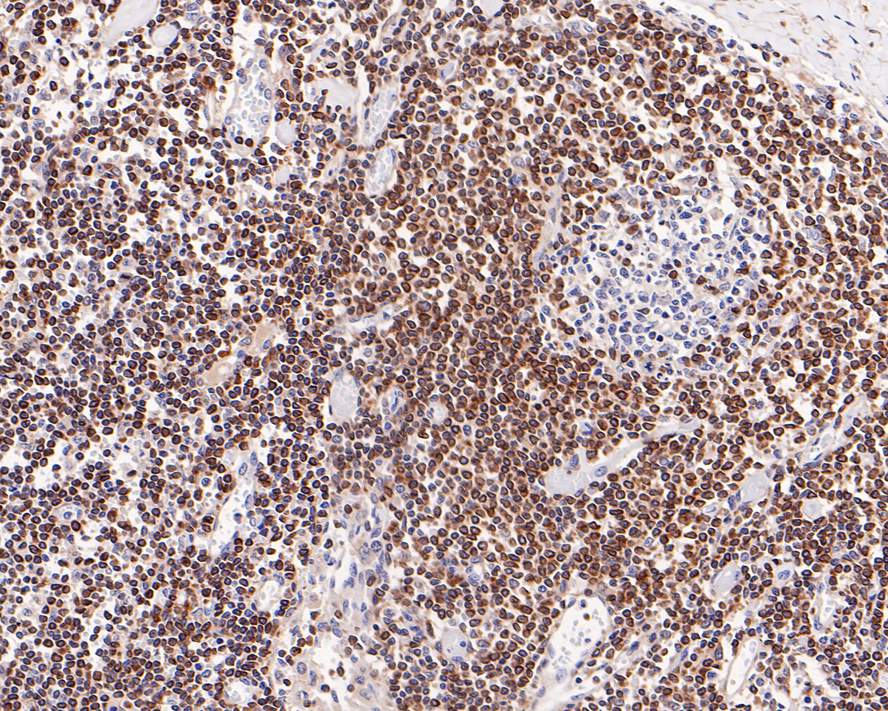

Immunohistochemical analysis of paraffin-embedded human B-cell lymphoma tissue with Rabbit anti-Bcl-2 antibody (HA721235) at 1/1,000 dilution.

The section was pre-treated using heat mediated antigen retrieval with Tris-EDTA buffer (pH 9.0) for 20 minutes. The tissues were blocked in 1% BSA for 20 minutes at room temperature, washed with ddH2O and PBS, and then probed with the primary antibody (HA721235) at 1/1,000 dilution for 1 hour at room temperature. The detection was performed using an HRP conjugated compact polymer system. DAB was used as the chromogen. Tissues were counterstained with hematoxylin and mounted with DPX.

Immunohistochemical analysis of paraffin-embedded human tonsil tissue with Rabbit anti-Bcl-2 antibody (HA721235) at 1/2,000 dilution.

The section was pre-treated using heat mediated antigen retrieval with Tris-EDTA buffer (pH 9.0) for 20 minutes. The tissues were blocked in 1% BSA for 20 minutes at room temperature, washed with ddH2O and PBS, and then probed with the primary antibody (HA721235) at 1/2,000 dilution for 1 hour at room temperature. The detection was performed using an HRP conjugated compact polymer system. DAB was used as the chromogen. Tissues were counterstained with hematoxylin and mounted with DPX.

Immunohistochemical analysis of paraffin-embedded human lymph nodes tissue with Rabbit anti-Bcl-2 antibody (HA721235) at 1/5,000 dilution.

The section was pre-treated using heat mediated antigen retrieval with Tris-EDTA buffer (pH 9.0) for 20 minutes. The tissues were blocked in 1% BSA for 20 minutes at room temperature, washed with ddH2O and PBS, and then probed with the primary antibody (HA721235) at 1/5,000 dilution for 1 hour at room temperature. The detection was performed using an HRP conjugated compact polymer system. DAB was used as the chromogen. Tissues were counterstained with hematoxylin and mounted with DPX.